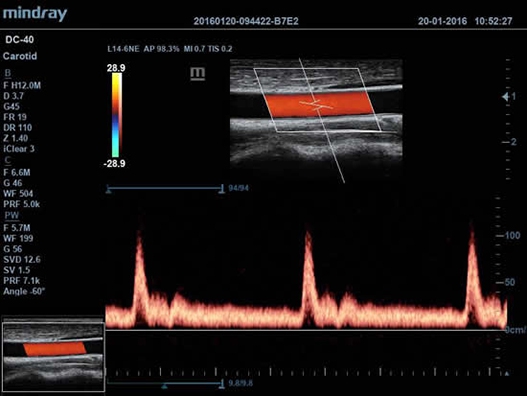

Mindray DC-40 - передовая УЗ-станция с выдающимися возможностями в области медицинской диагностики. Компания Mindray разработала это устройство с учетом высоких требований врачей к качеству изображения и быстродействию. DC-40 обеспечивает высокое качество изображения и точность диагностики, что является необходимым в повседневной практике врачей. Технологии, применяемые в этом устройстве, позволяют получать четкое и детализированное изображение.

Технологии iBeam, iClear и iScape, применяемые в DC-40, позволяют получать объемные изображения высокого качества без помех и зернистости в зоне сигнала. Панорамная визуализация с расширенным обзором анатомических структур решает проблемы сложных диагнозов, которые ранее создавали значительные трудности в ультразвуковой диагностике.

• Функция Auto IMT автоматически измеряет толщину комплекса интима-медиа.

• Auto IMT Package – измерения и анализ толщины комплекса интимамедии (КИМ) сонной артерии;

• Мультичастотный линейный датчик Mindray L14-6

• Высокочастотный линейный датчик 38 мм Mindray l14-6NE